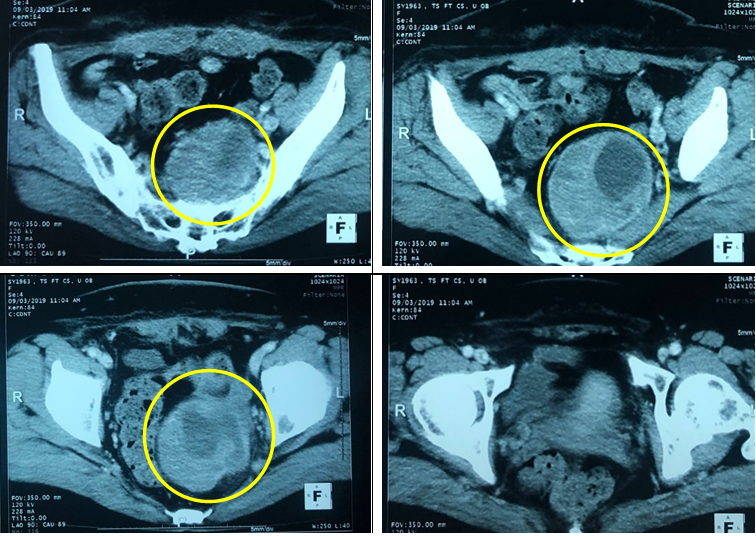

-        Chụp cắt lớp vi tính ổ bụng: Khối vùng tiểu khung kích thước 78x80mm nằm cạnh buồng trứng trái đẩy trực tràng ra sau, khối có vỏ dầy không đều, bên trong có chứa phần đặc và dịch, phần đặc có ngấm thuốc cản quang sau tiêm.

Hình 1. Hình ảnh khối u vùng tiểu khung trên chụp căt lớp vi tính ổ bụng (vòng tròn vàng)